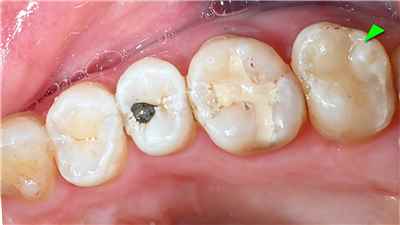

치아 변색 내부 원인

여드름 치료를 위해서 미노사이클린 복용으로 약간 파랗게 변색된 치아 (출처: Lee Ann Brady DMD)